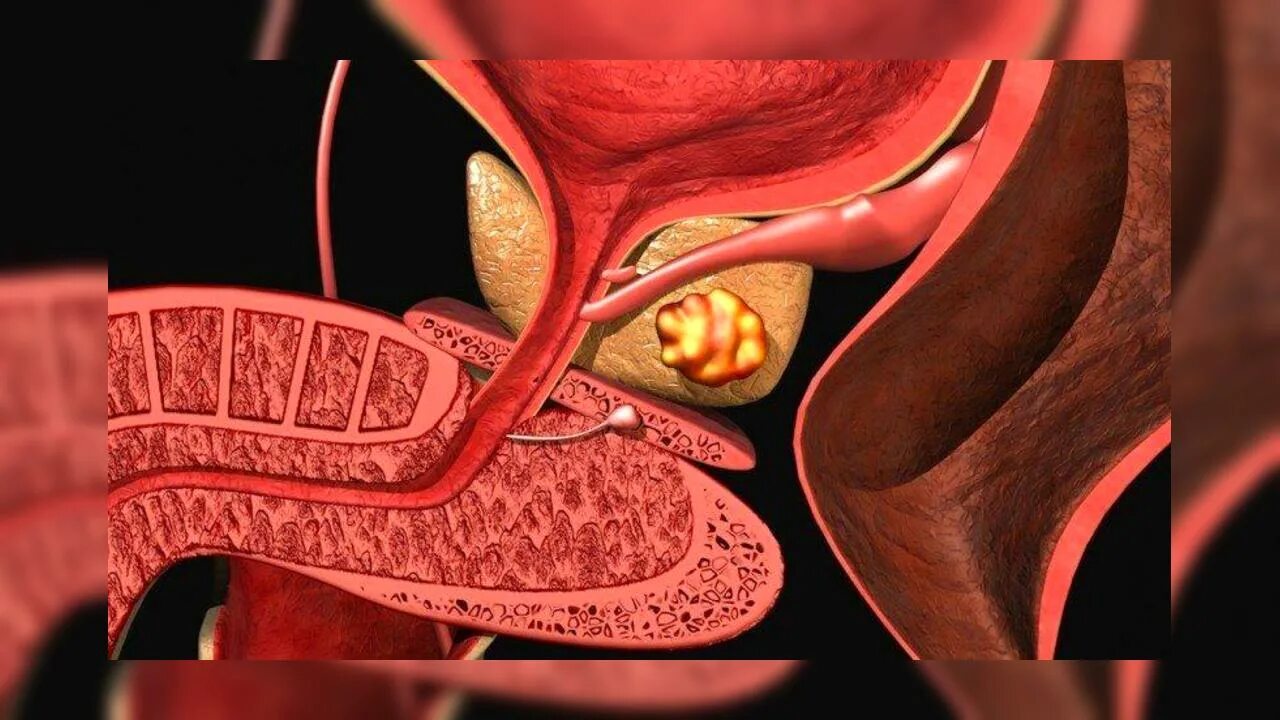

Опухоль аденомы простаты симптомы. Раковые заболевания простаты. Раковая опухоль простаты. Предстательная железа у мужчин онкология

Опухоль аденомы простаты симптомы. Раковые заболевания простаты. Раковая опухоль простаты. Предстательная железа у мужчин онкология Злокачественная опухоль простаты. Злокачественное новообразование предстательной железы. Злокачественные новообразования простаты

Злокачественная опухоль простаты. Злокачественное новообразование предстательной железы. Злокачественные новообразования простаты Карцинома предстательной железы. Злокачественное новообразование предстательной железы. Cancer предстательной железы. Аденома предстательной железы – это опухоль

Карцинома предстательной железы. Злокачественное новообразование предстательной железы. Cancer предстательной железы. Аденома предстательной железы – это опухоль Предстательная железа, Prostata. Аденома предстательной железы. Карцинома предстательной железы. Злокачественное новообразование предстательной железы

Предстательная железа, Prostata. Аденома предстательной железы. Карцинома предстательной железы. Злокачественное новообразование предстательной железы Cancer предстательной железы. Аденокарцинома предстательной железы. Онкология предстательной железы

Cancer предстательной железы. Аденокарцинома предстательной железы. Онкология предстательной железы Опухоль предстательной железы у мужчин. Злокачественное новообразование предстательной железы. Эктопия предстательной железы. Карцинома предстательной железы

Опухоль предстательной железы у мужчин. Злокачественное новообразование предстательной железы. Эктопия предстательной железы. Карцинома предстательной железы